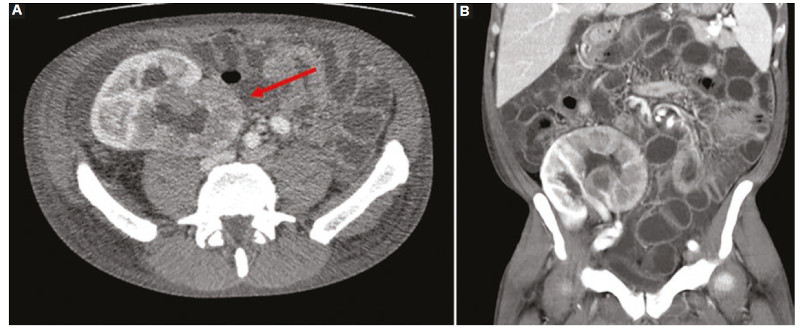

El riñón se compromete principalmente en los casos de trasplante renal, reportándose entre el 10 y 75% de estos casos según variados estudios11,37,40. Las manifestaciones más frecuentes la representan como una masa que rodea el hilio renal, con compromiso subsecuente vascular; y un patrón infiltrativo difuso del parénquima6,11,38) (Fig. 7).

En el caso de una masa renal, esta se presenta con conservación del tamaño renal; mientras que si se manifiesta con un patrón infiltrativo se observará un aumento de tamaño renal con posible extensión extrarrenal y compromiso de órganos adyacentes, permitiendo esto iniciar la sospecha de la entidad38.